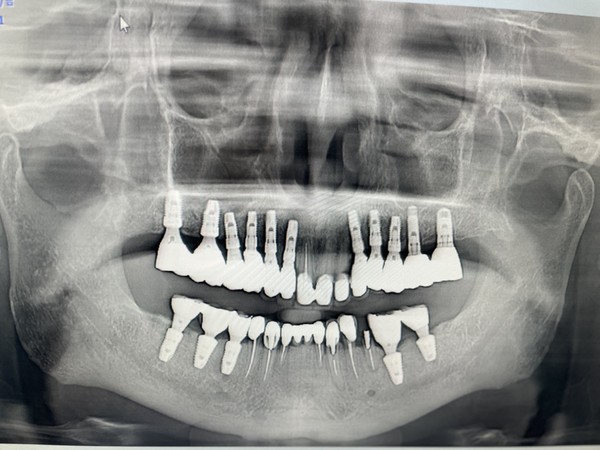

rainbow CT는 보다 넓은 FOV 지원으로 정확한 진단을 가능케 해 박 원장의 만족도를 높였다.

박 원장은 CT 촬영 시 Sinus 뿐만 아니라 최소한 Maxillary ostium까지의 사이즈는 꼭 지원해야 한다고 말한다.

상악동 수술을 위해 CT 판독을 하는 과정에서 Obstructed Ostium을 발견하고 배농술을 진행하는 경우가 있다. 이때 다른 CT들은 FOV가 충분하지 않기에 제한된 이미지로 진단을 내려야 하고 작은 상의 이미지를 보는 것이 불편하다고 했다.

rainbow CT는 콘빔 Stiching 없이도 충분한 FOV를 제공해 한 번의 촬영만으로도 진 단에 필요한 정보를 충분히 얻을 수 있다. 특히나 상악, 하악, 상하악을 찍을 수 있어 가장 만족한다고 했다.